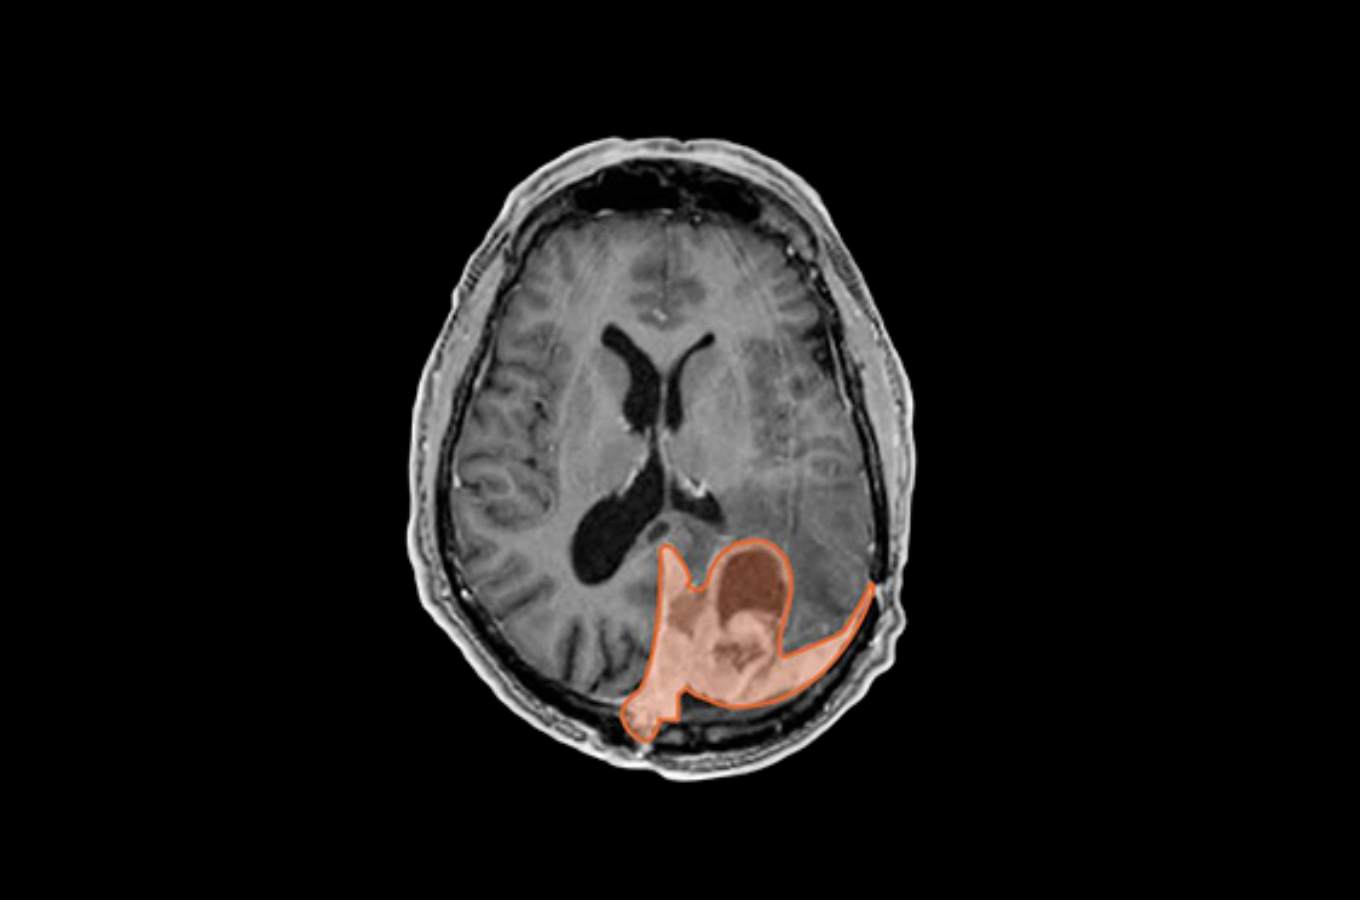

A brain tumor is usually serious. But there are different grades. About 65% to 70% of meningiomas are grade 1 tumors. These are regarded as nonmalignant and are usually surgically removed or treated with radiotherapy. If there is remaining tumor, it can also be treated with radiotherapy. Up to 95% of grade 1 patients are alive five years later, depending on age and the amount of tumor removed.

Malignant meningioma makes up about 5% of cases. These grade 3 tumors are likely to recur, and five-year survival rates are lower at about 50%.